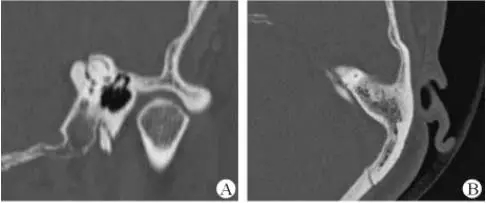

1、上半規管裂綜合征

內耳結構非常微妙。即使是內耳中大頭針樣的孔洞也能造成平衡失調。患者常常不敢進行如走路或轉頭的日常活動。此罕見疾病,醫學專家預估至少影響著人口的1%??稍斐蓯盒?,眩暈以及對噪聲極高的敏感性。病人還常常抱怨他們能聽到血管跳動的聲音。其中一位患者曾告訴耳科專家,他都能聽到自己轉動眼睛的聲音。

診斷及治療

醫生若懷疑此病將會安排內耳CT掃描。在大多數案例中,一旦此病被耳鼻喉科醫生或其它聽力健康專家確診,則可實行手術治療。外科手術風險包含聽力損失以及神經損傷;重建及復原需內耳的治療以及大腦的重塑。